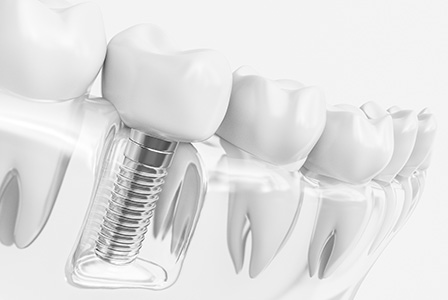

インプラントとは、歯を失った部分の顎の骨に人工の歯根(インプラント体)を埋め込み、その上に人工の歯を装着する治療方法です。

見た目も自然で、機能的にも「自分の歯のように」しっかり噛めるのが大きな特徴です。骨としっかり結合するため、違和感がほとんどなく、周囲の歯に負担をかけないという点でも、他の治療法よりも優れているとされています。

歯を失ってしまった所にインプラントを埋め込み、その上に被せ物をしていく治療方法になります。失った前後の健康な歯を削って治療することもありませんし、前後の歯に負担をかけることもありません。